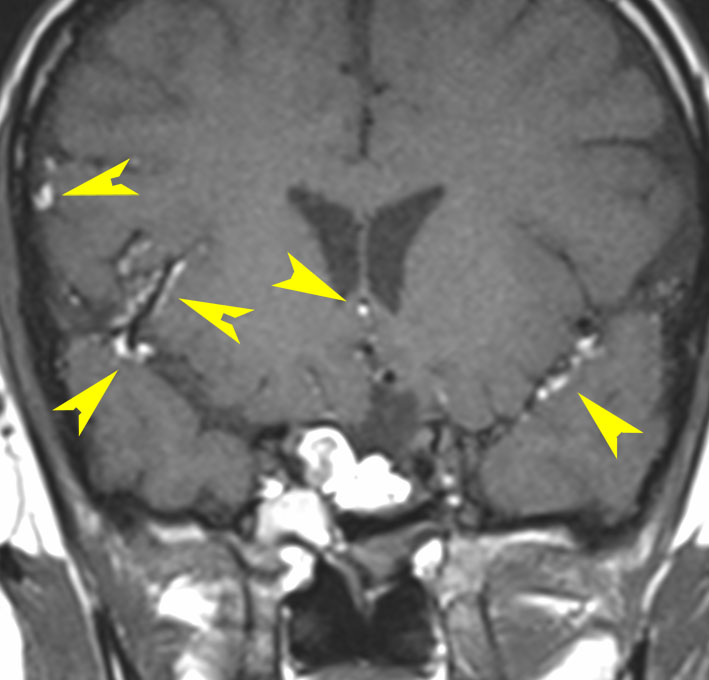

頭痛と嘔吐という髄膜刺激症状で発症しました。鞍結節部の類皮のう胞が破れたものです。黄色い矢印の先の白い点々にみえるのが散らばった内容物です。油滴です。

ちょっと専門的な知識